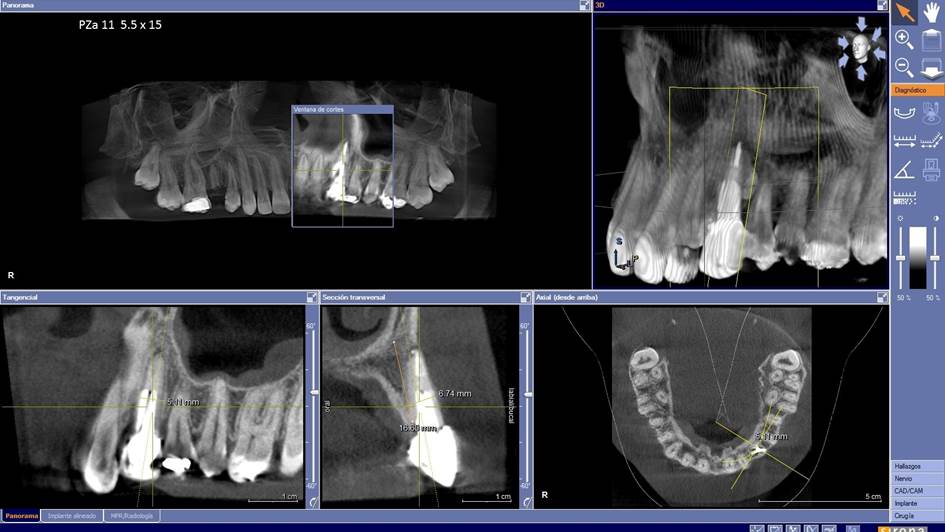

Clinical case: Extraction, immediate implant placement, & provisionalization

- Courtesy of Dr. Iulian Filipov, Romania -

Keywords

AnyRidge, R2GATE, guided surgery, immediate placement, immediate provisionalization, initial stability, Dr. Iulian Filipov, #25, maxillary posterior, immediate loading, Mega ISQ

Products:

AnyRidge implant system, R2GATE, MEGA ISQ, Digital prosthesis